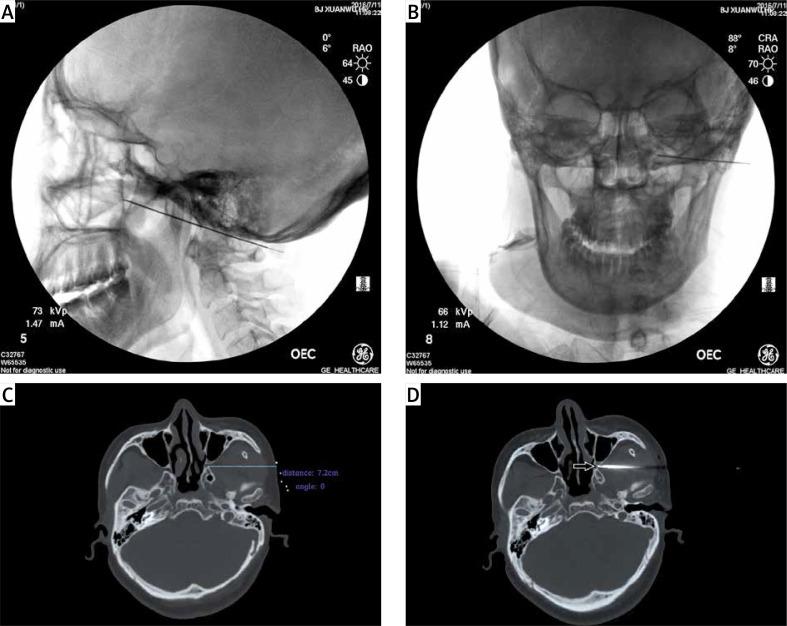

Although the sphenopalatine ganglion (SPG) has been considered a site of therapeutic potential for cluster headache (CH), the optimal technique of SPG is still to be determined. Low-temperature plasma radiofrequency ablation (LTPRA) has been proposed as an alternative treatment for several neuropathic pain diseases.

The patients with CH, who achieved temporary pain relief following SPG block, treated using LTPRA between January 2015 and October 2017 were reviewed. Seventy-six patients were included: 50 patients suffered from episodic CH and the remaining 26 patients from chronic CH. The primary outcomes were clinical improvement rate, defined as the percentage of partial and complete pain relief results at 1 day, 12 months, and 24 months of follow-up after the operation.

Clinical improvement rates were 92.3%, 92.3% and 73.1% in chronic CH and 73.1%, 84% and 68% in episodic CH at each follow-up time point, respectively. 3 chronic CH patients and 7 episodic CH patients showed no pain relief after the operation. Drooping eyelids were found in 2 cases, one recovered at the 3-month follow-up but another one did not in the 24-month follow-up. No serious complications occurred intraoperatively or postoperatively.

LTPRA can be considered an effective and alternative surgical modality in treating patients with chronic and episodic CH, based on SPG block.